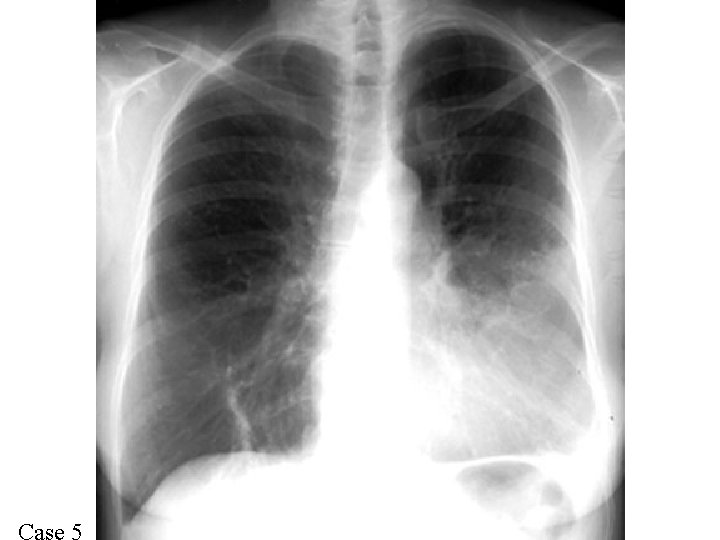

Case 1